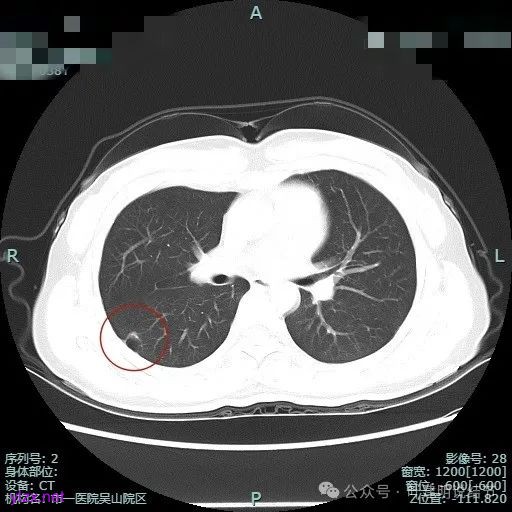

非薄层平扫上这个层面比较明显,似一囊腔,壁厚薄欠均匀。